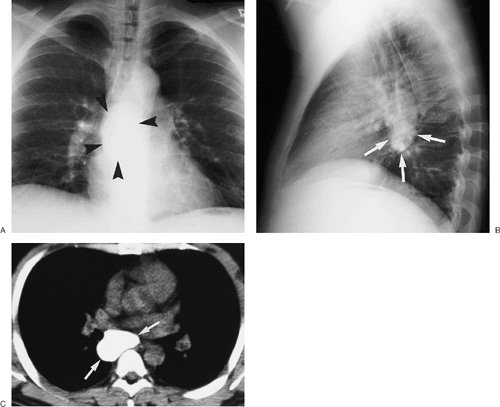

FIGURE 6-23. Pulmonary histoplasmosis. A: PA chest radiograph shows right paratracheal (solid arrow) and bilateral hilar (dashed arrows) lymphadenopathy. B: CT scan shows bulky right paratracheal lymphadenopathy (arrow). C: CT scan at a more inferior level shows bilateral hilar (solid arrows) and subcarinal (dashed arrow) lymphadenopathy. The appearance is indistinguishable from that of sarcoidosis.